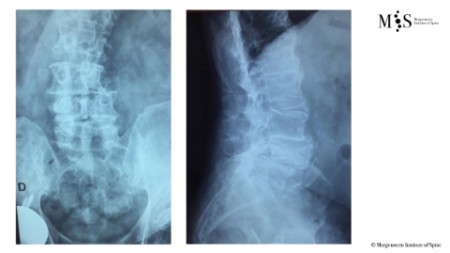

Ejemplo caso clínico cifoplastia

Comparación pre- y post-operatoria de una cifopastia cementada

Mujer, edad 55 años, Fractura aplastamiento derecho de L2

Antes 1

Después 1

Antes 2

Después 2